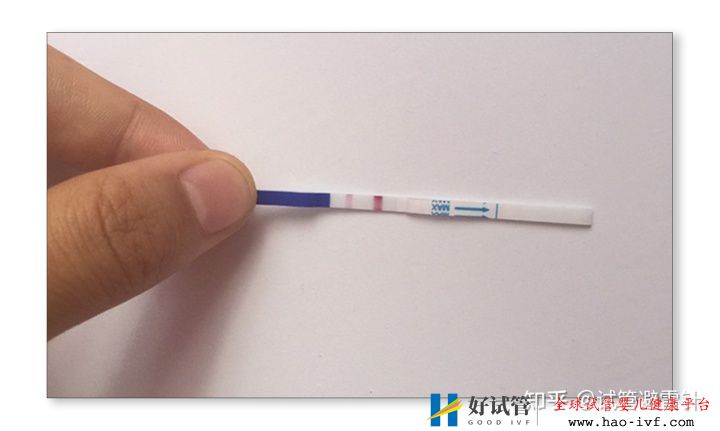

试管婴儿费用大约多少2021年:国内试管之(8)验孕

这个过程中,患者一般会在在第14天左右做B超检查,看看胚胎是否着床,尿检,抽血,并在第二天做血液取样,看看血值是否翻倍,在移植后的第30天,还有抽血看血值,看看是否有胎心和胎芽。

在移植后的第14天,用验孕测试纸可以来检验是否怀孕。试纸可以在药店买,2元一张的就可以了,不用太贵的。也建议不要过早测试,以免影响你的情绪,因为之前有些朋友在第5天就开始做检测,其实没有这样的需要,因为当时根本无法检测是否怀孕,即使检测到也是由于药物的影响,假阳性。